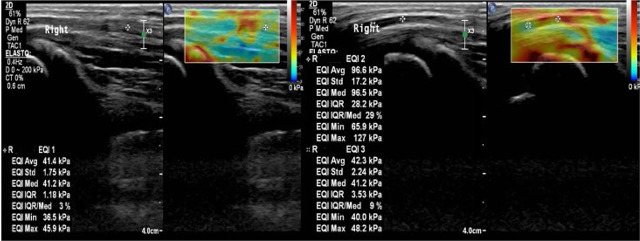

Clasificación de casos severos

Aunque la SWE no fue útil para diferenciar entre grados de CTS (leve, moderado y severo), sí demostró capacidad significativa para distinguir los casos severos exclusivamente en la entrada del túnel. Un punto de corte ≥126 kPa permitió predecir casos graves con sensibilidad del 100% y especificidad del 77% (AUROC: 0.871), lo que resulta relevante para la toma de decisiones quirúrgicas.

Elastografía en paciente con síndrome del túnel del carpo severo